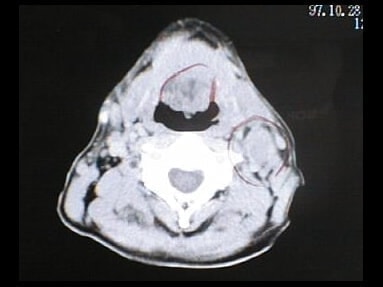

CT画像比較

入院当時CT画像①

入院3か月後癌消滅CT画像①